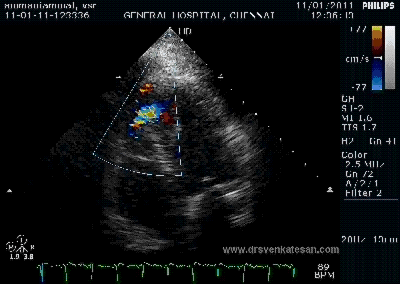

Color flow showing significant shunting from LV to RV.This shunt depends upon the LV contractile function, LVEDP and ofcourse the RV pressure

If there is severe RV dysfunction or bi ventricular dysfunction flow across the defect is inconspicuous.Brisk left to right shunting may be an indirect marker for good LV systolic function and absence of significant pulmonary hypertension.Both imply a better outcome.